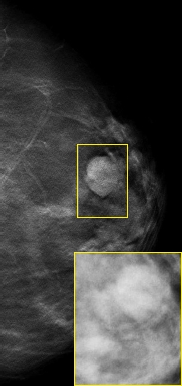

左图: 右图: |

当面对底扫描样本的乳腺断层摄影,滤波反投影算法(产生伪影和噪音)已经不再为理想的选择方案。滤波反投影算法为了努力抑制伪影,同时也滤除了真实结构。艾蒙斯先进的重建算法的确在控制病人接触放射剂量的同时最优了影像质量(如右图断层图像效果)。